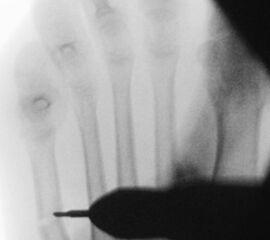

=> Risikoabwägung der radiologisch leicht erhöhten Strahlenbelastung intraoperativ

In der minimalinvasiven Fußchirurgie ist es unabdingbar, die Fräse in ihrer Position zum Knochen radiologisch zu kontrollieren, damit vulnerable Wachstumsfugen oder angrenzende Gelenke nicht verletzt werden. Zu diesem Zweck werden mit einem Bildwandler während der Operation die genaue Position der Fräse und der Osteotomieverlauf überprüft, was die Strahlenbelastung im Vergleich zu offenen Verfahren erhöht. Diese Strahlenbelastung hat potenziell einen schädigenden Einfluss auf den noch blutbildenden Knochen von Heranwachsenden. Gesicherte Landmarken am Fuß können die notwendige Zahl der Röntgenbilder und damit die Strahlung minimieren. Ist es erforderlich, mehrere Knochen zu osteotomieren, wie zum Beispiel im Bereich der Kleinzehen, werden anhand der Landmarken kleine Injektionsnadeln auf Höhe der geplanten Osteotomien vorgelegt und radiologisch im Bildwandler (BV) dokumentiert (Abb. 11). Ein solches Bild schafft eine gute Orientierung, sodass auf radiologische Kontrollen intraoperativ weitestgehend verzichtet werden kann.

Abb. 11: Lokalisation mehrerer Stichinzisionen mit einem Röntgenbild.